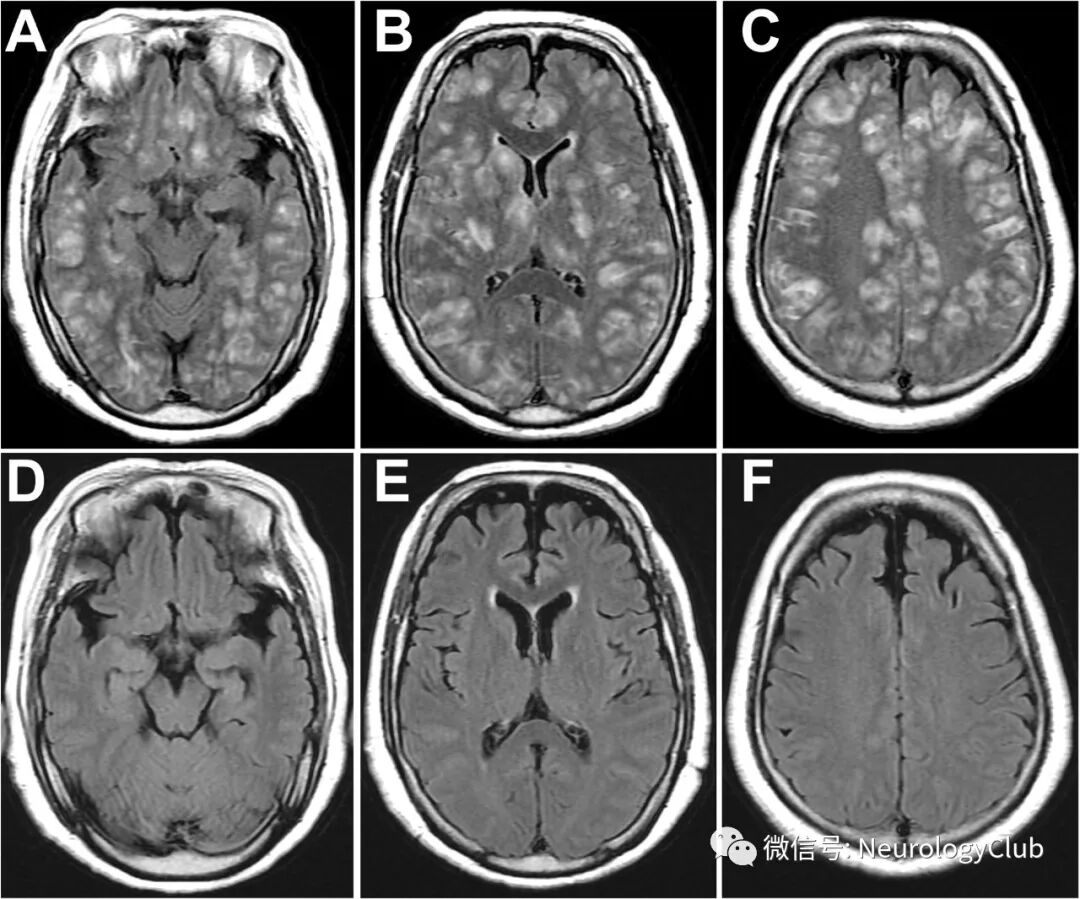

(图:A-C:FLAIR提示双侧皮质下白质和深部灰质如丘脑和基底节片状高信号;D-F:随访复查MRI可见病灶完全消失

头颅MRI提示急性播散性脑脊髓炎(图1A-C)。实验室检查提示血常规和C反应蛋白正常。脑脊液细菌和结核检测阴性。血清和脑脊液未见病毒抗体。激素冲击治疗5天,患者症状明显改善。2周后完全恢复(图1D-F)。